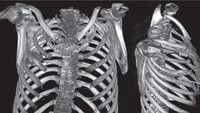

Setelah ditelusuri, pisau itu sudah menancap sejak 8 tahun lalu. Dalam sebuah perkelahian, ia mengalami luka parah di beberapa area tubuh tapi tidak sadar telah ditusuk pisau. (Foto: Journal of Surgical Case Reports)

"Rontgen dada lateral awal menunjukkan adanya benda logam tersangkut di bagian tengah dada, dengan bayangan samar di sekitarnya yang mengindikasikan hematoma terlokalisasi kronis yang mengeluarkan cairan, atau fibrosis pasca-trauma, kemungkinan besar akibat luka tusukan pisau pasien," tulis dokter dalam studi kasusnya. (Foto: Journal of Surgical Case Reports)